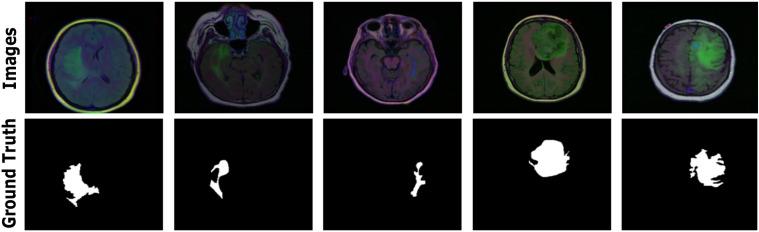

DSIT UNet a dual stream iterative transformer based UNet architecture for segmenting brain tumors from FLAIR MRI images.

Brain tumor segmentation remains challenging in medical imaging with conventional therapies and rehabilitation owing to the complex morphology and heterogeneous nature of tumors. Although convolutional neural networks (CNNs) have advanced medical image segmentation, they struggle with long-range dependencies because of their limited receptive fields. We propose Dual-Stream Iterative Transformer UNet (DSIT-UNet), a novel framework that combines Iterative Transformer (IT) modules with a dual-stream encoder-decoder architecture. Our model incorporates a transformed spatial-hybrid attention optimization (TSHAO) module to enhance multiscale feature interactions and balance local details with the global context. We evaluated DSIT-UNet using three benchmark datasets: The Cancer Imaging Archive (TCIA) from The Cancer Genome Atlas (TCGA), BraTS2020, and BraTS2021. On TCIA, our model achieved a Mean Intersection over Union of 95.21%, mean Dice Coefficient of 96.23%, precision of 95.91%, and recall of 96.55%. BraTS2020 attained a Mean IoU of 95.88%, mDice of 96.32%, precision of 96.21%, and recall of 96.44%, surpassing the performance of the existing methods. The superior results of DSIT-UNet demonstrate its effectiveness in capturing tumor boundaries and improving segmentation robustness through hierarchical attention mechanisms and multiscale feature extraction. This architecture advances automated brain tumor segmentation, with potential applications in clinical neuroimaging and future extensions to 3D volumetric segmentation.